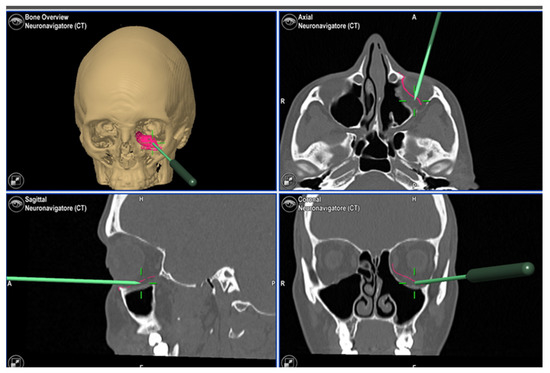

3. Case Report 2